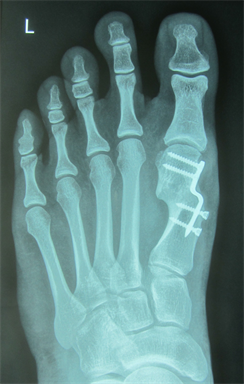

Figure 4. Patient Nr. 1: Recurrance of preoperated hallux valgus and hammertoe II.

Figure 5. Patient Nr. 1. Correction of a pathological DMAA without loss of length. Distal fragment has only a point contact to the proximal bone partner. Additional Akin osteotomy and PIP arthrodesis and FDL tranfer on the 2nd toe.

Figure 6. Patient Nr. 1. After 6 months the bone healing is completed with no loss of correction. Immediate full weigh bearing was allowed.